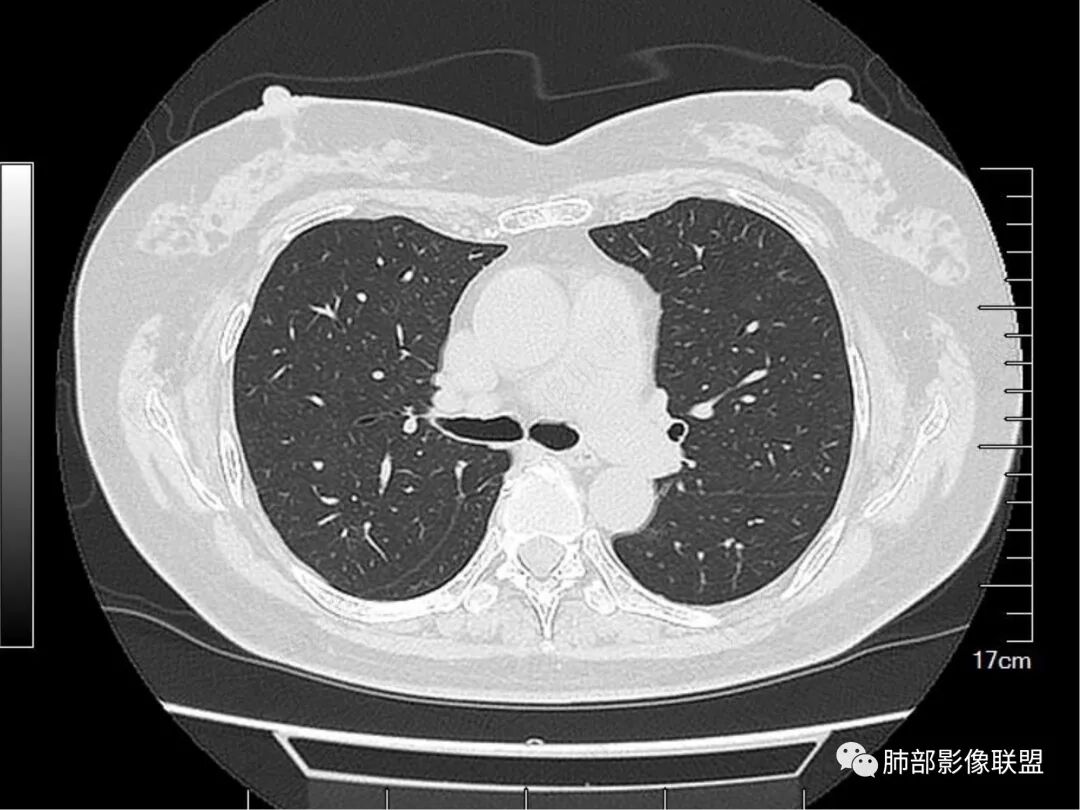

1. 病史简单,老年女性,体检发现肺结节,1年后复查病灶可疑稍增大。

2. 首先定位。这个病变位于胸膜下、肺内病变没问题。请仔细看箭头所示的条索影,我感觉像小叶间隔。

伪影太重了。仔细看,这里是两个支气管分支。而且倾向于小支气管或细支气管水平